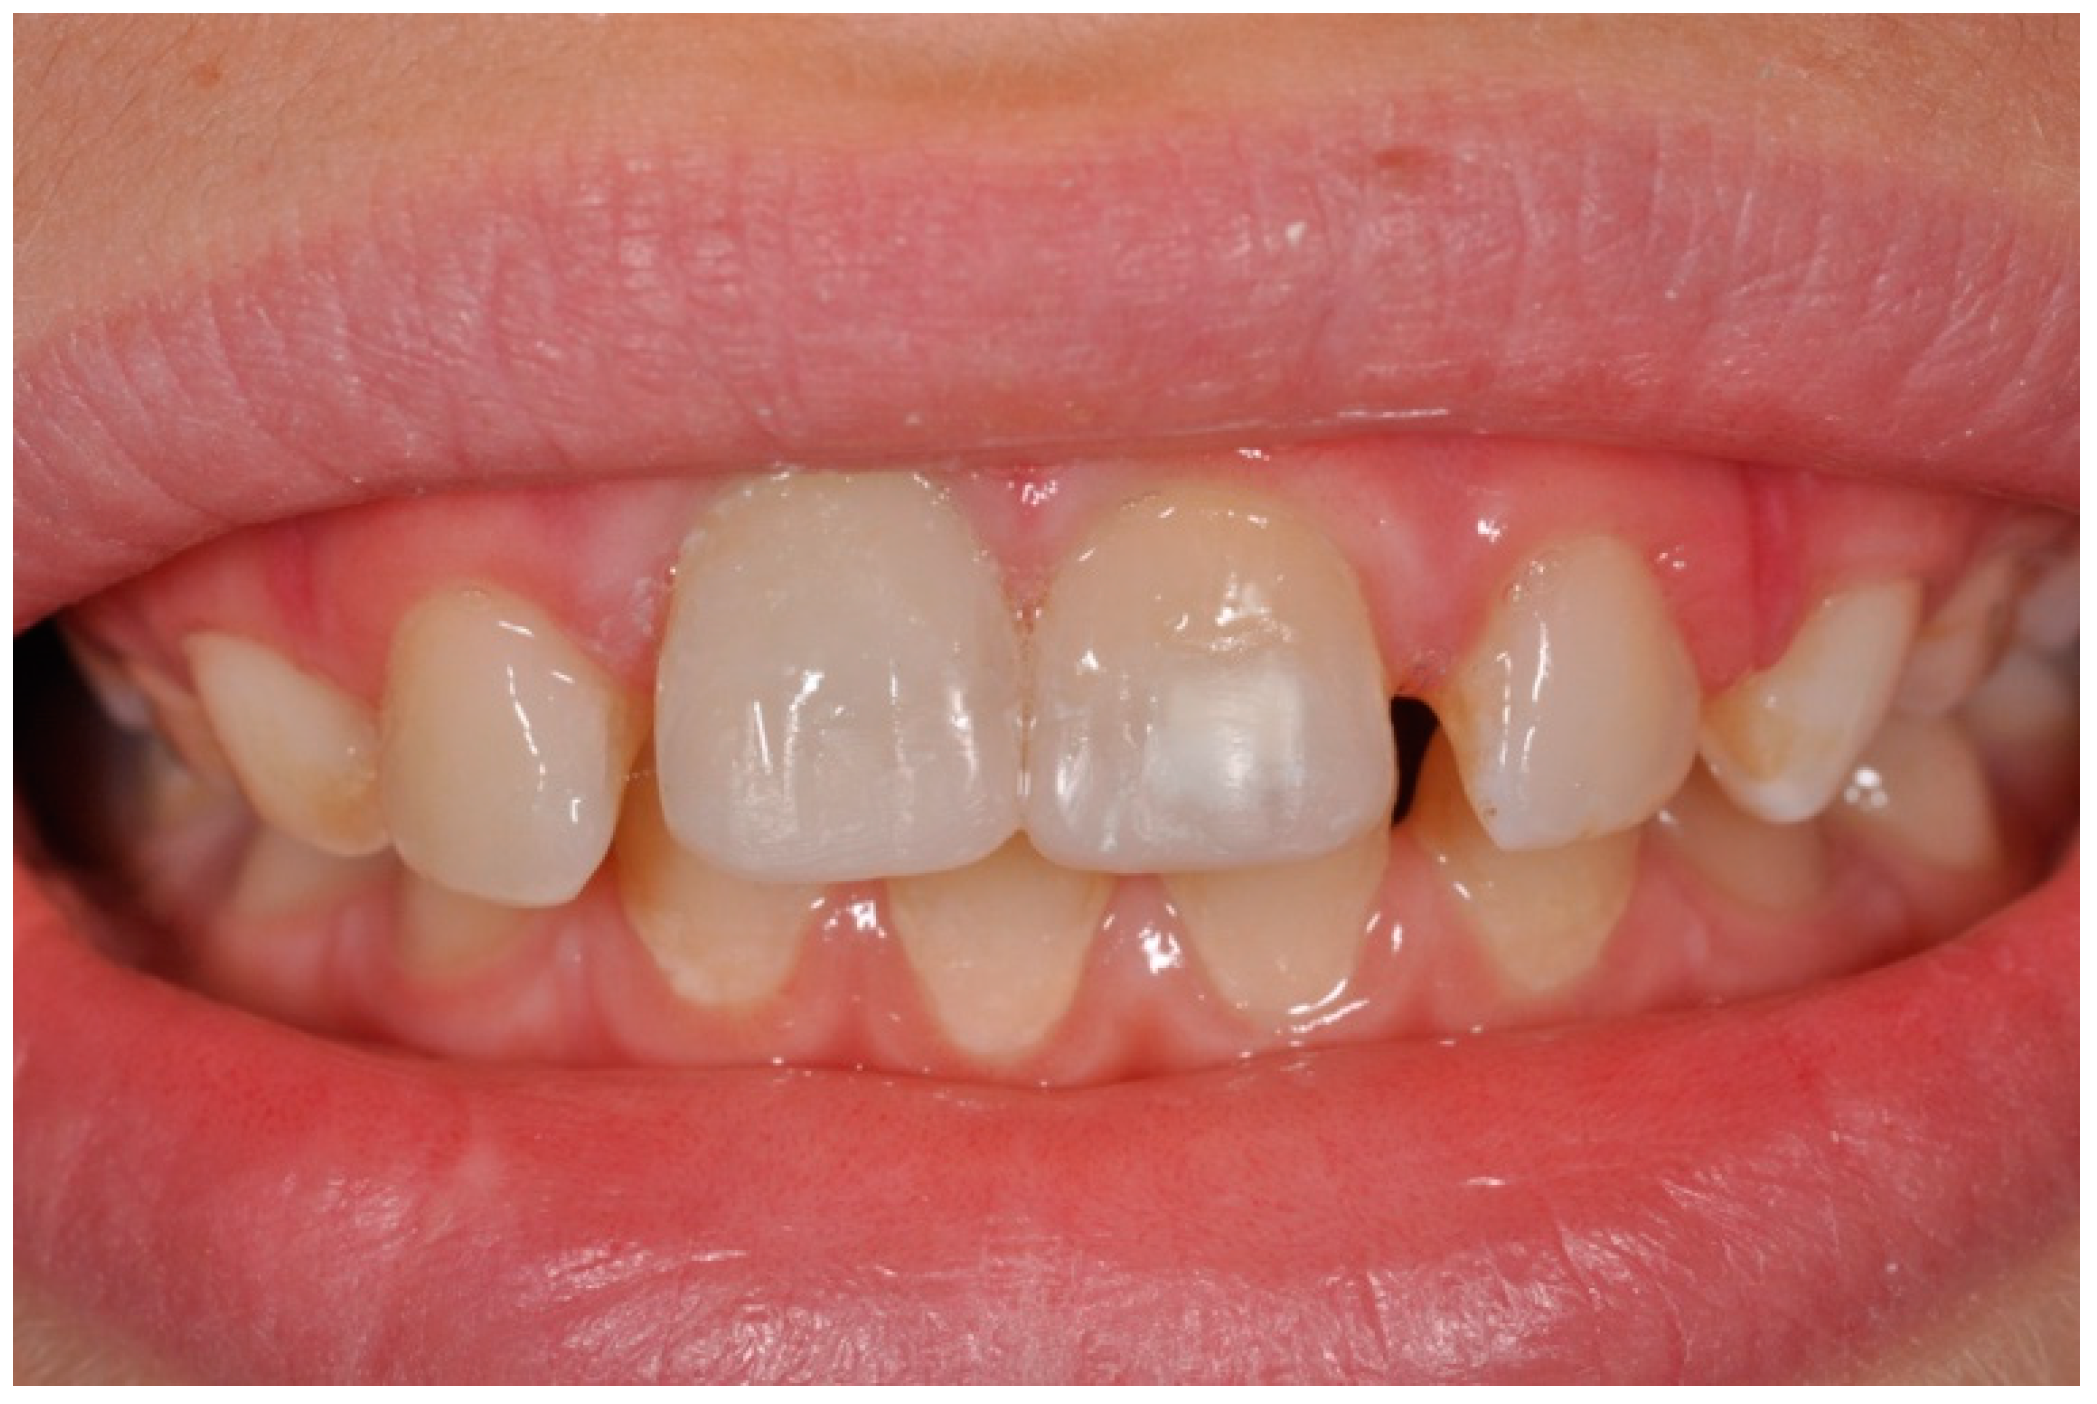

2. Case Report